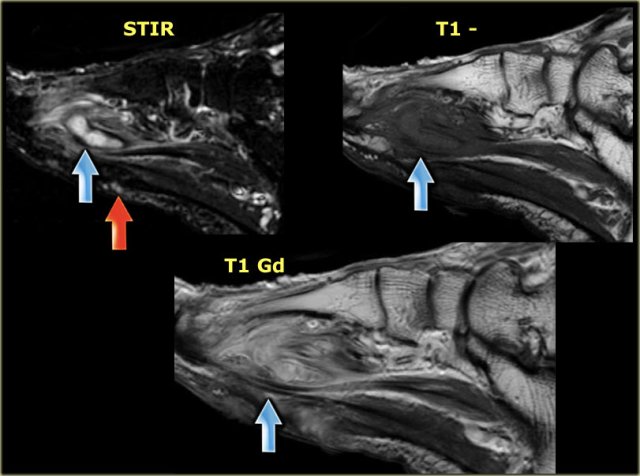

Here, images of a patient with a small cutaneous defect and subcutaneous edema at the metatarsals.

A secondary sign, an abscess, is shown in the forefoot, with high signal intensity on STIR, low or intermediate signal on intensity T1W, and ring-enhancement of the borders showing high signal intensity on T1+Gd.